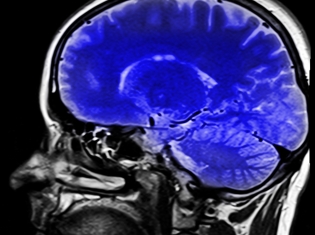

High-resolution magnetic resonance imaging (MRI) was conducted to show the size of study participants’ brains. In addition, the athletes were given a computerized test of their memory and other cognitive skills that concussion can effect.

The researchers found that players with and without a history of concussions had a smaller hippocampus that the non-athletes. In addition, players who had been diagnosed with concussion had a smaller hippocampus than players who had not been diagnosed with concussion.

The left hippocampus of the players who had been diagnosed with concussion was 23.8 percent smaller, on average, than the left hippocampus of non-athletes. The left hippocampus of players who had not been diagnosed with concussion was 14.1 percent smaller than that of non-athletes.

The right hippocampus of players with a history of concussions was 25.6 percent smaller than that of the non-players. The right hippocampus of players with no history of concussions was 16.7 percent smaller than that of non-players.